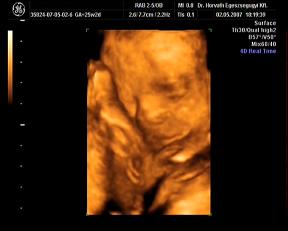

Nán-dorka: nagyon cukipofi a bébitek. És milyen szépen látszik az arca!!! És annyira klassz, hogy tele vagy jóhírrel, végre!!! :D A down kórt felejtsd el!!! Nincs semmi gond, minden rendben a kislányotokkal!!! Hidd el!!! A fejmérete pont a korának megfelelő.

Megjöttem az uh-ról. :) Minden ok. :)

Most is megmutatta milyen van, és kislány. :))

Most már elhiszem, h 2x mondták. :)

képet kaptam, de nem lett túl jó. :(

Hajni, örülök a jó híreknek! Azért ha van kedved, a nem-olyan-jó képet is rakd be! :)

Néhány kép, nagyon kis drága volt, szépen mutatta magát:

egy 2D-s profil

És néhány 3D-s:

Hát ilyenek vagyunk a 25. héten.:D